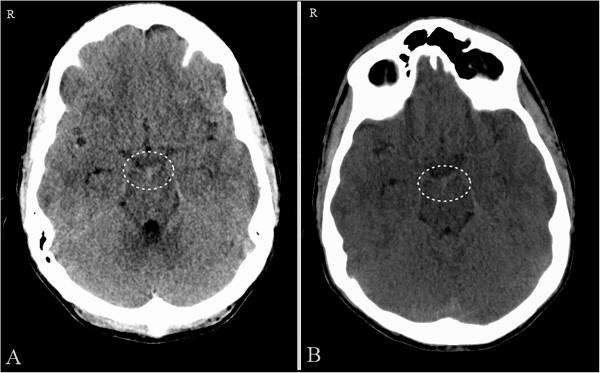

A 39-year-old Caucasian man presented with sudden onset headache associated with diplopia. His computed tomography scan revealed perimesencephalic subarachnoid hemorrhage. A cerebral angiogram showed no apparent source of bleeding. He was treated conservatively and discharged after 1 week without any neurological deficits. The older brother of the first case, a 44-year-old Caucasian man, presented 1.5 years later with acute onset of headache and his computed tomography scan also showed perimesencephalic non-aneurysmal subarachnoid hemorrhage. He was discharged home with normal neurological examination 1 week later. Follow-up angiograms did not reveal any source of bleeding in either patient.

一名39岁的白种男性因突发头痛伴复视而就诊。他的计算机断层扫描显示中脑周围蛛网膜下腔出血。脑血管造影未显示明显的出血源。他接受了保守治疗,1周后出院,无任何神经功能缺损。第一例患者的哥哥,一名44岁的白种男性,1.5年后因急性头痛就诊,其计算机断层扫描也显示中脑周围非动脉瘤性蛛网膜下腔出血。1周后他神经系统检查正常出院。随访血管造影未发现任何一例患者有出血源。